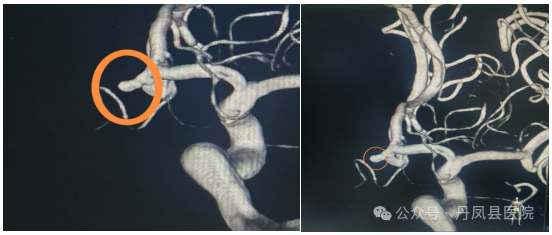

8月22日,为患者行全脑血管造影术,造影证实患者为大脑前交通动脉瘤。面对这一生命威胁,神经外科团队与患者家属进行了深入细致的沟通,详尽阐述了手术风险与医院现有的技术实力及上级医院专家支持。患者家属听后,同意在丹凤县医院接受颅内动脉瘤介入栓塞术。

图为造影发现动脉瘤8月28日,在唐都医院神经外科姜海洋教授的现场指导下,神经外科王龙珍主任、刘建锋主治医师及张永昌、赵斌轲医师联合麻醉科、介入室进行了多学科讨论,评估手术安全,最终,成功为患者实施了颅内前交通动脉瘤介入栓塞术,手术顺利,动脉瘤体被致密填塞,术后患者麻醉清醒,无神经功能受损表现。![]()